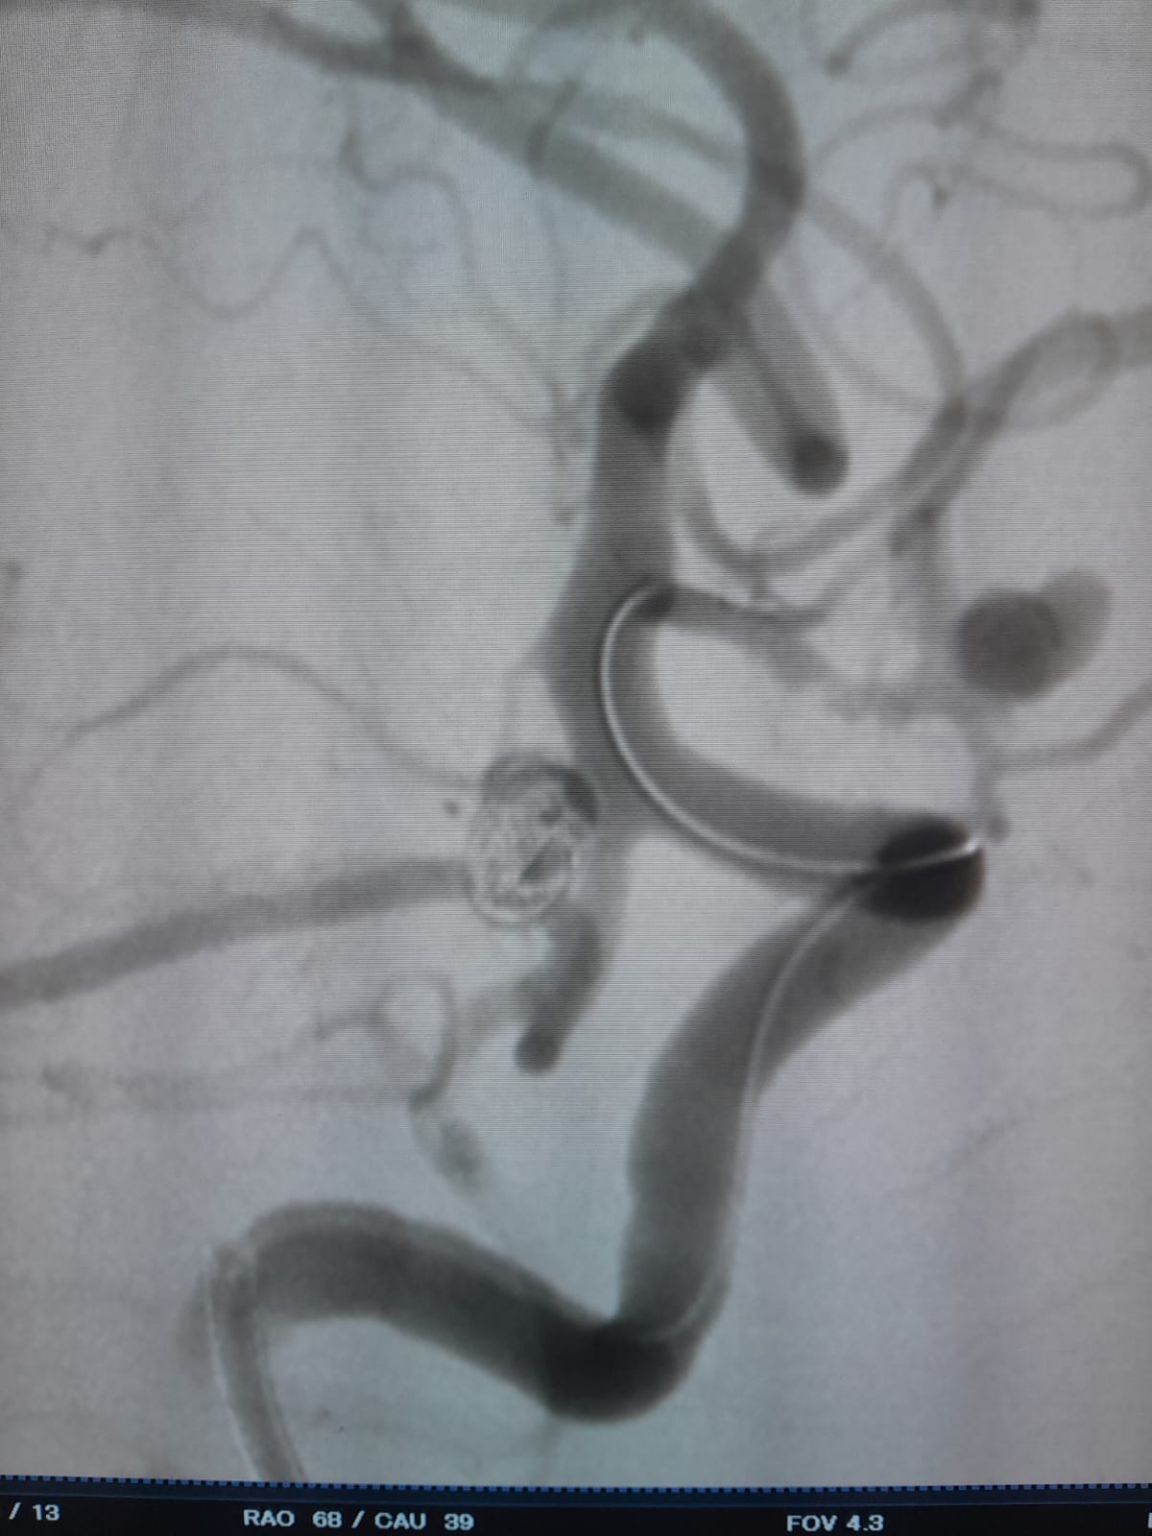

During follow-up, residual filling was noted in the previously treated posterior communicating artery aneurysm. The team re-accessed the site using Frepass® Disposable Microcatheter (TJMC18 Plus) and successfully deployed a Nuva® Flow Diverter (TJED-D-4.5-16), which demonstrated ideal wall apposition and excellent flow diversion, leading to highly satisfactory treatment outcomes.

Nuva®: Effective Solution for Recurrent Aneurysms

An effective solution for aneurysms with residual filling or recurrence after initial coiling.

Excellent wall apposition and stable flow diversion.

Nuva® simplifies retreatment, reduces procedural complexity, and improves long-term outcomes.